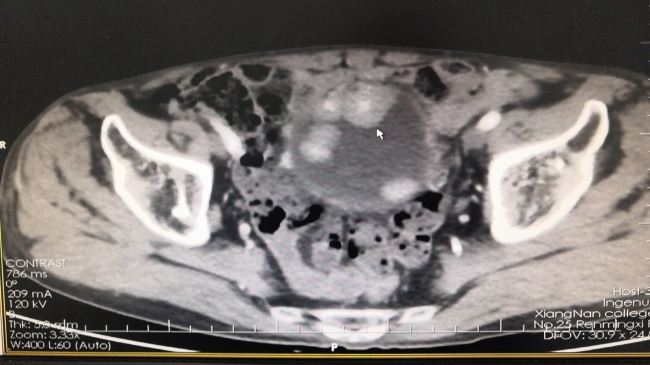

唐建生主任团队立即为曾叔叔安排了多学科联合会诊,并根据他的临床表现、既往病史及相关检查资料,同时予以完善三大常规、尿培养、肝肾功能、凝血功能、泌尿系增强CT、病理活检等检查。检查结果显示,曾叔叔确诊为膀胱低级别浸润性尿路上皮癌,且肿瘤呈多发趋势,肿瘤瘤体也比较大,对比何叔叔当时的情况要更为复杂,需要实施手术难度高,操作步骤复杂的腹腔镜下膀胱全切除+回肠代膀胱手术(膀胱癌根治术)手术治疗。